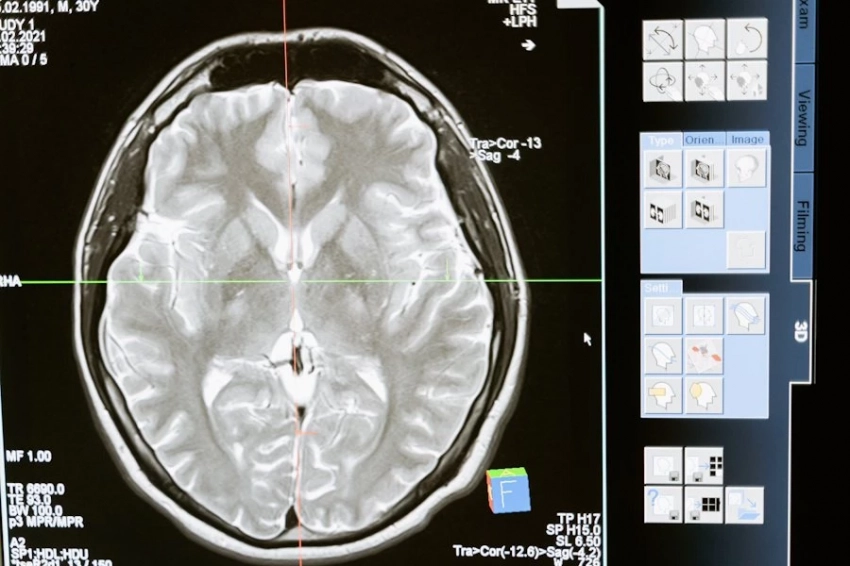

Всего было обследовано 739 когнитивно здоровых участников, 389 из которых были женщинами в возрасте 70 лет. Мозг этих людей был исследован с помощью МРТ, что позволило команде оценить возраст мозга с помощью алгоритма на основе искусственного интеллекта.

В дополнение к МРТ головного мозга были взяты образцы крови для измерения липидов, глюкозы и маркеров воспаления. Кроме того, участники прошли различные когнитивные тесты и были собраны данные о факторах образа жизни (например, физической активности и медицинских заболеваниях).

Возраст мозга участников оценивался ИИ в среднем в 71 год. Исследователи также определили так называемый разрыв в возрасте мозга, который представляет собой разницу между предполагаемым биологическим возрастом мозга и хронологическим возрастом.